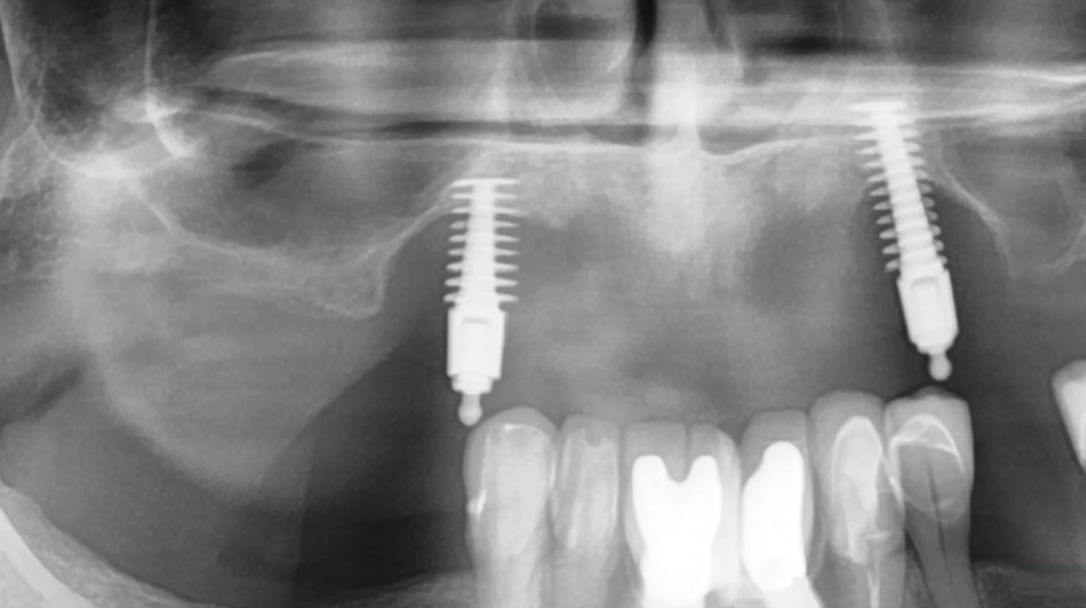

First comes evaluation, which often includes a CBCT scan. This scan helps the dentist see the implant’s position and bone condition. Dr. Harris emphasizes that this step is crucial to plan the removal safely and avoid damage to surrounding tissues.

After waiting: Your dentist re-evaluates bone with CBCT scanning. If bone volume and quality are good, a new implant can often be placed successfully.